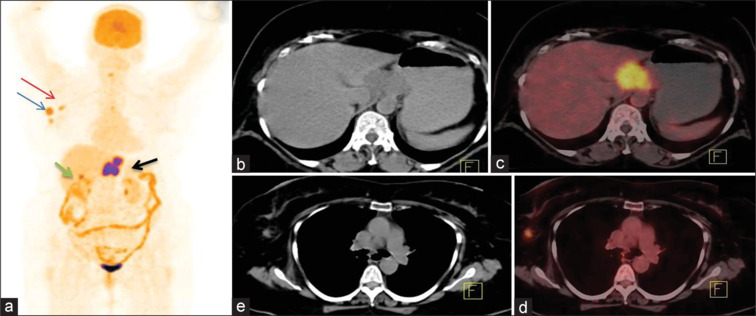

Results: Among total n = 74 (42 males and 32 females with mean age 59.4 ± 11.4; range 35-86 years) patients, SCC was seen in 78.4% and AC in 21.6% of patients. There is a progressively increased SUVmax value of primary tumor with nodal and distant metastases. 18F-FDG PET/CT showed disease of Stage I-II in 12.1%, Stage III in 20.2%, Stage IVA in 25.6%, and Stage IVB in 41.8% patients. There is agreement between 18F-FDG PET/CT and CECT chest and abdomen in the evaluation of regional lymph nodes (37.8% vs. 36.4%; κ - 0.96), nonregional lymph nodes (24.3% vs. 20.2%; κ -0.74), and distant organ involvement (21.6% vs. 17.5%; κ -0.82). In addition, 18F-FDG PET/CT found synchronous malignancies in 4.0% of patients.

Conclusion: 18F-FDG PET/CT metabolic parameters help in identifying metastatic involvement in morphologically equivocal and clinically suspicious lesions in carcinoma esophagus patients. Being a whole-body imaging modality, 18F-FDG PET/CT has inbuilt advantage to detect occult, distant metastases, and synchronous malignancies for effective staging and improving plan of clinical management.